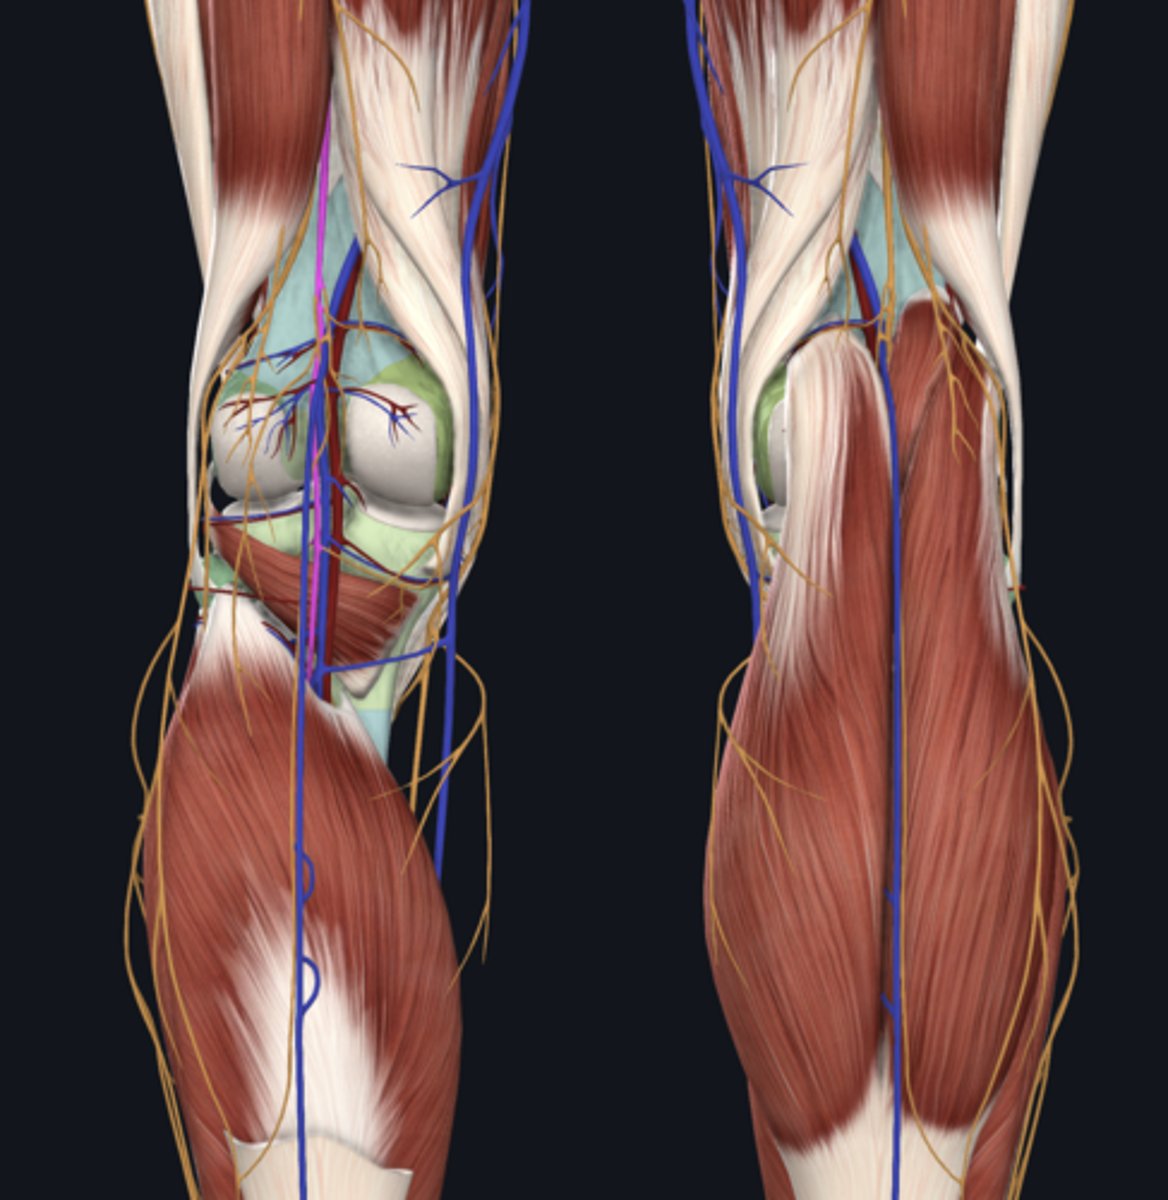

Popliteal artery

artery

Popliteal vein

vein

Tibial nerve

nerve

Medial head of gastrocnemius

Lateral head of gastrocnemius

Soleus

Plantaris